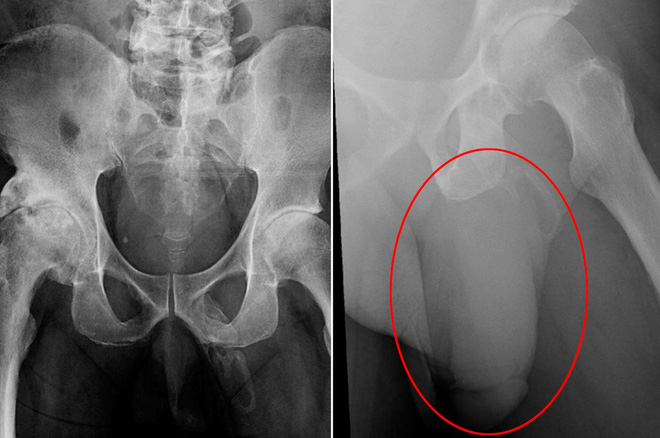

Hình ảnh chụp X-quang cho thấy xương chậu không bị vỡ nhưng lại thấy các tế bào xương hình thành trong dương vật của người đàn ông này, được gọi là dương vật “hóa thạch”.

Khi ở bệnh viện, các bác sĩ lo rằng ông ta còn gãy thêm một số xương khác nữa nên đã chụp X-quang vùng xương chậu.

Kết quả cho thấy vùng xương chậu của ông ra hoàn toàn bình thường, không hề có dấu hiệu nứt vỡ, thay vào đó, các bác sĩ lại phát hiện ra các tế bào xương đang hình thành trong dương vật của người đàn ông này khiến nó đang dần "hoá thạch".

Hình ảnh chụp X-quang của bệnh nhân.